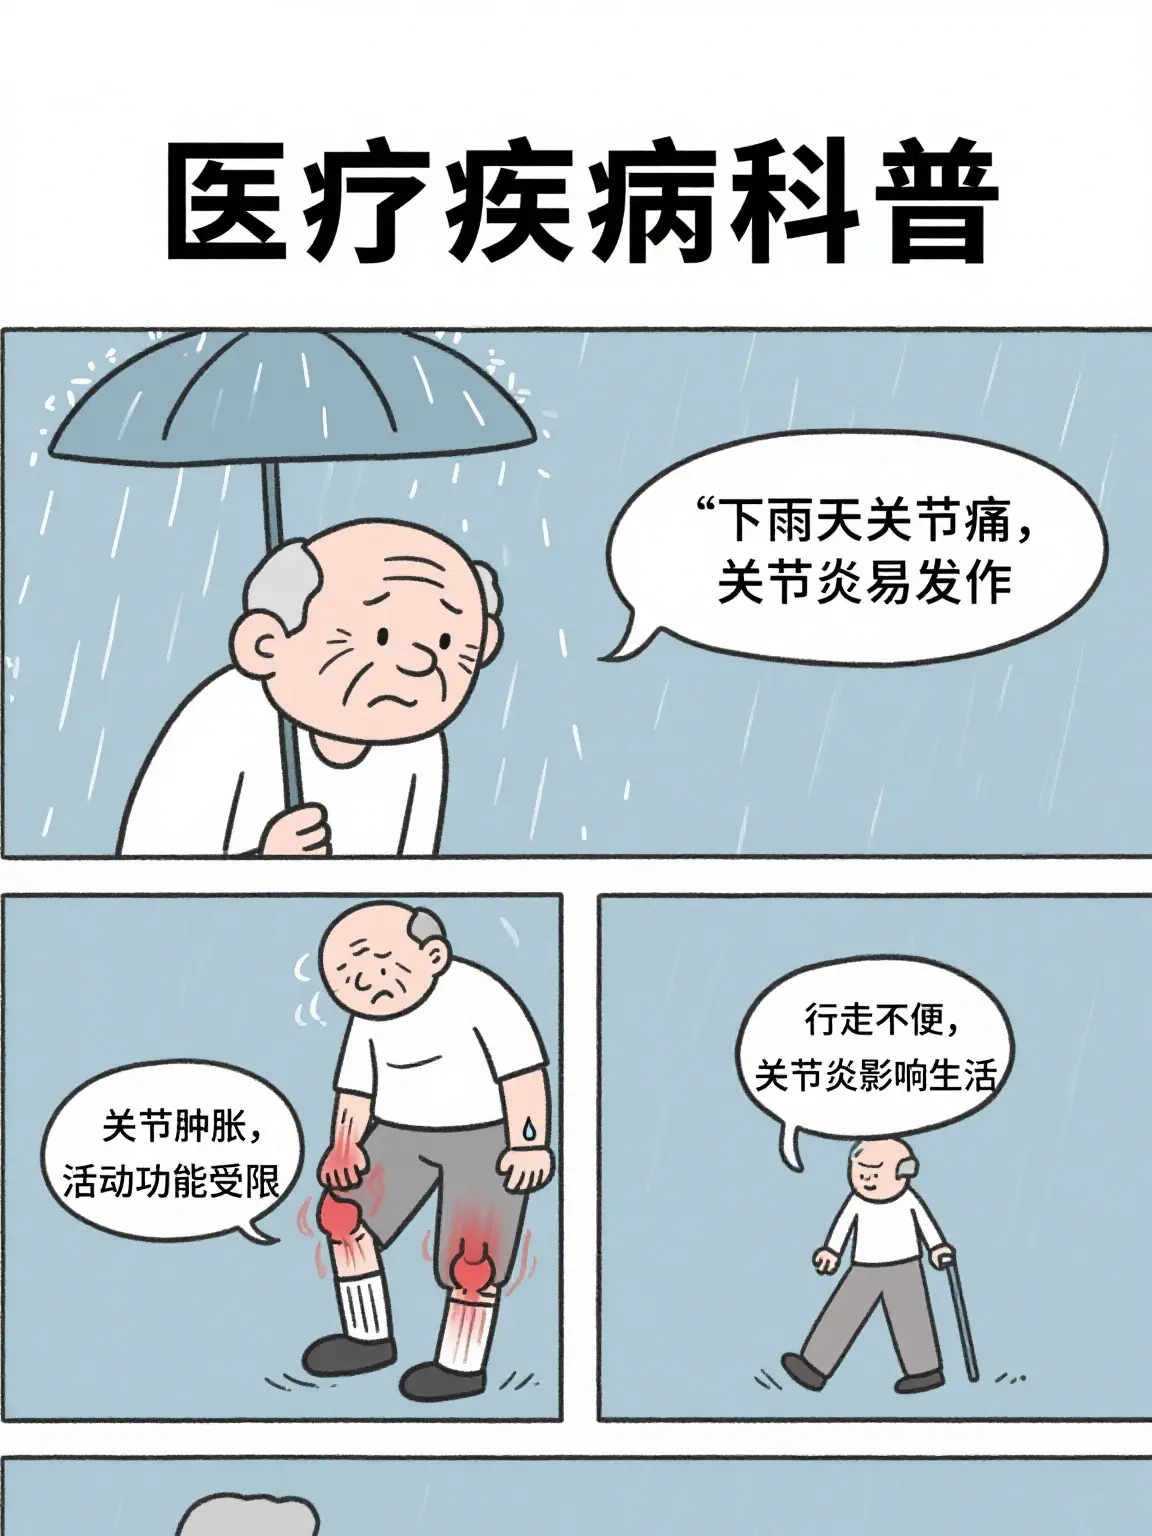

醫療宣傳知識科普...

269人浏覽中

醫療宣傳知識科普...

521人浏覽中